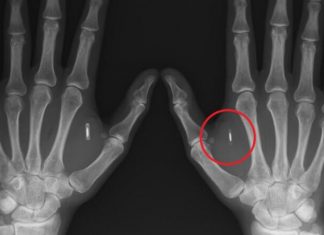

5 историй о том, как люди добровольно вживили себе чипы под кожу

Компания Neuralink, которая была основана Илоном Маском в 2016 году, уже сумела имплантировать чипы в мозги свиньи и обезьяны. В первом случае компания успешно проследила за мозговой активностью животного, а во втором — позволила примату сыграть в компьютерную игру...